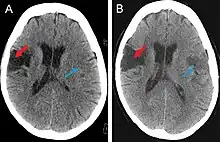

This computer-tomography type of imaging is one of the most used in any clinical environment and although it can detect some of the brain areas affected by a stroke or a trauma it does not provide the same acuity as the magnetic resonance imaging. CT scans can also reveal, in patients with the syndrome, the bilateral cortical infarcts located in the posterior frontal region involving the opercular areas.[3]